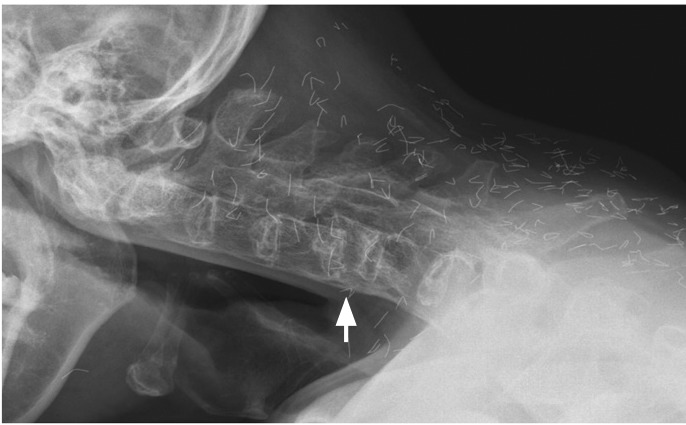

Figure 1

Plain radiograph shows total ankylosis of the cervical spine, a C5 vertebral body fracture with anterior dislocation of C4 on C5 (arrow), and numerous thin foreign bodies along the spine.

A 51-year-old man with a 22-year history of ankylosing spondylitis who had been treated with nonsteroidal anti-inflammatory drugs and infliximab presented with severe posterior neck pain, which had been aggravated after he fell backwards 3 months earlier. The neurological examination was normal. Plain radiographs showed total ankylosis of the cervical spine and a C5 vertebral body fracture with anterior dislocation of C4 on C5 (Fig. 1). There were numerous thin pieces of foreign material along the spine (Fig. 1). The patient said he had undergone Korean traditional gold thread acupuncture therapy, which had not been effective. Gadolinium-enhanced fat-suppressed T1-weighted magnetic resonance imaging showed a recent compression fracture of the C5 vertebral body and resultant spinal cord compression (Fig. 2), as well as an old compression fracture of C7. For cervical spine fractures in ankylosing spondylitis, conservative treatment with gentle low-weight cervical traction can be performed initially, in the absence of a neurologic deficit. However, secondary neurological deterioration occurs frequently due to the delayed dislocation at the original fracture site, and surgical treatment is generally recommended. On surgical exploration of our patient, the C5 fracture was found to be stable and surgical f ixation was not done. The cervical spine is the most frequent site of acute spinal fracture in ankylosing spondylitis, particularly at C5-6 and C6-7. Since the cervical fractures in ankylosing spondylitis are usually unstable, with a high risk of neurological deficits, our patient was lucky not to have had any significant neurological complications.